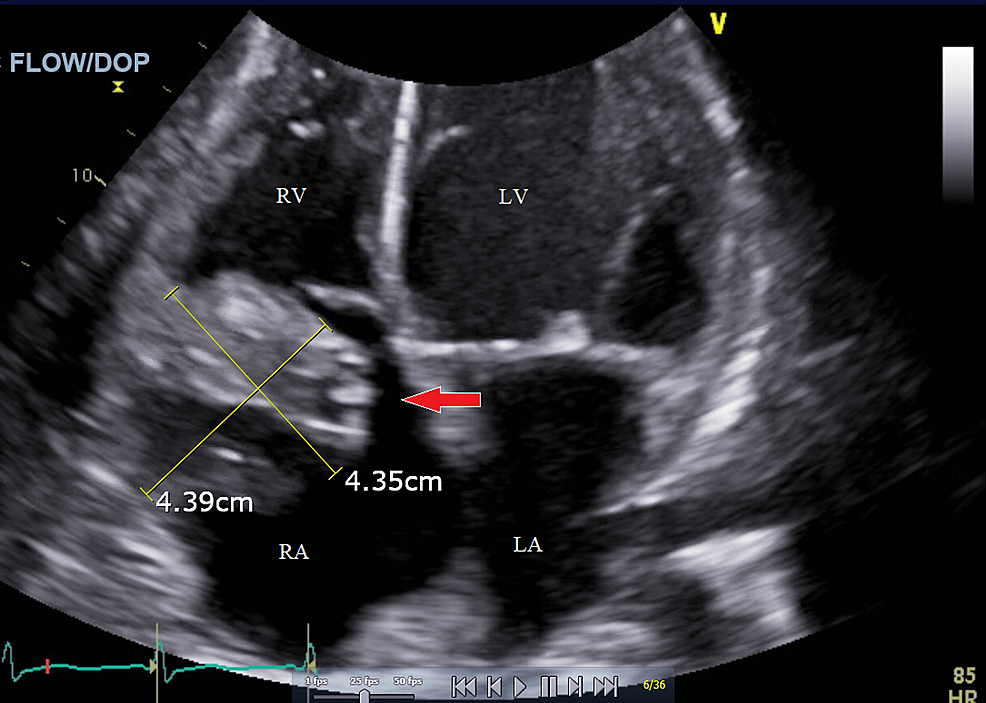

The Use of AngioVac in a Patient With Severe Infective Endocarditis Where Open Heart Surgery Is Contraindicated: A Case Report

Infectious endocarditis of the tricuspid valve (TV) is a common complication of intravenous (IV) drug use. Endocarditis caused by viridans streptococci can lead to heart valve vegetations, which may be...

This therapy, in conjunction with intravenous antibiotics and hemodialysis, successfully sterilized the vegetation, prevented worsening presentation, and averted life-threatening complications, although severe tricuspid regurgitation persisted. Based on the findings of this case, the AngioVac device is a safe and effective treatment option...